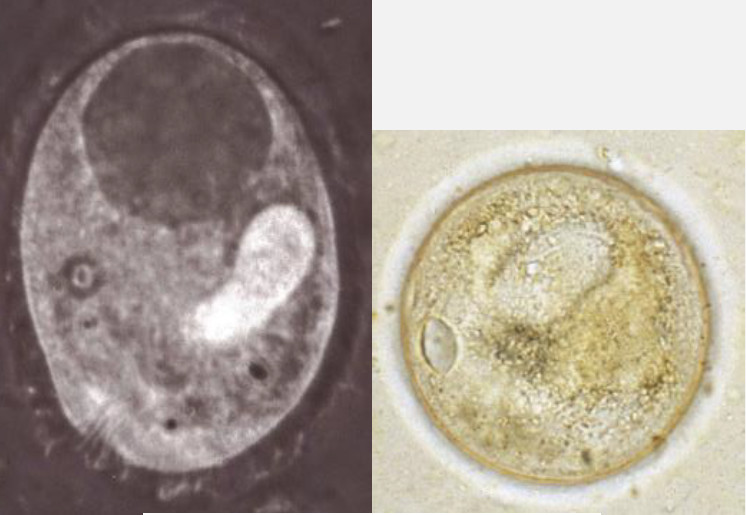

Name this Apicomplexa

Protists > SAR > Apicomplexa > Gregarines > Cryptosporidium

Cryptosporidium: Oocysts contain ____ sporozoites

4

Cryptosporidium: Oocysts are _____ infective when passed

Immediately

Cryptosporidium: where do sporozoites released from oocysts invade in the host?

Cells in microvillous border

Cryptosporidium: can cause _____infection

Oocysts can excyst before leaving the host leading to autoinfection

Cryptosporidium: Prepatent period

Short, 2-7 days in calves